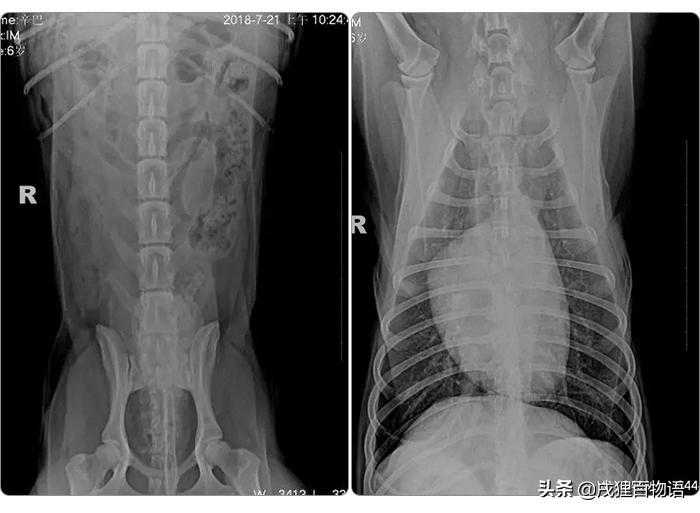

今天的主角是辛巴,一只雄性拉布拉多宝宝,有一天辛巴突然出现了尿血症状。主人带着它去附近医院检查出膀胱结石,医生建议手术。主人选择了保守治疗,但是一段时间后并没有好转。

医生测出辛巴体温为37.8℃,精神状态尚可,可视粘膜粉色,耳道、皮肤尚可,听诊心肺正常。

血常规正常

血压正常

大量膀胱结实